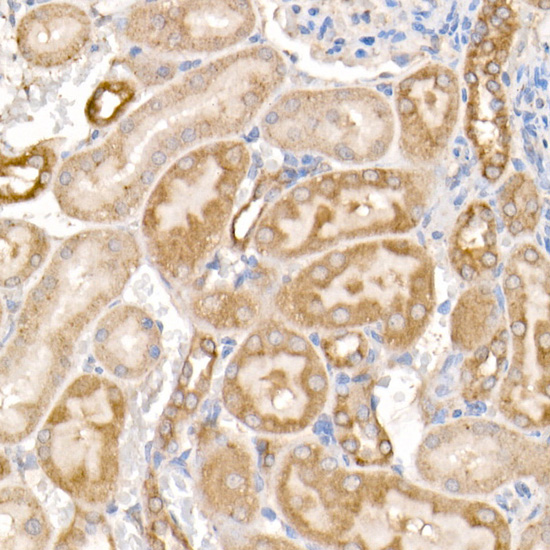

Immunohistochemistry of paraffin-embedded mouse kidney using MMP14/MT1-MMP Rabbit pAb.